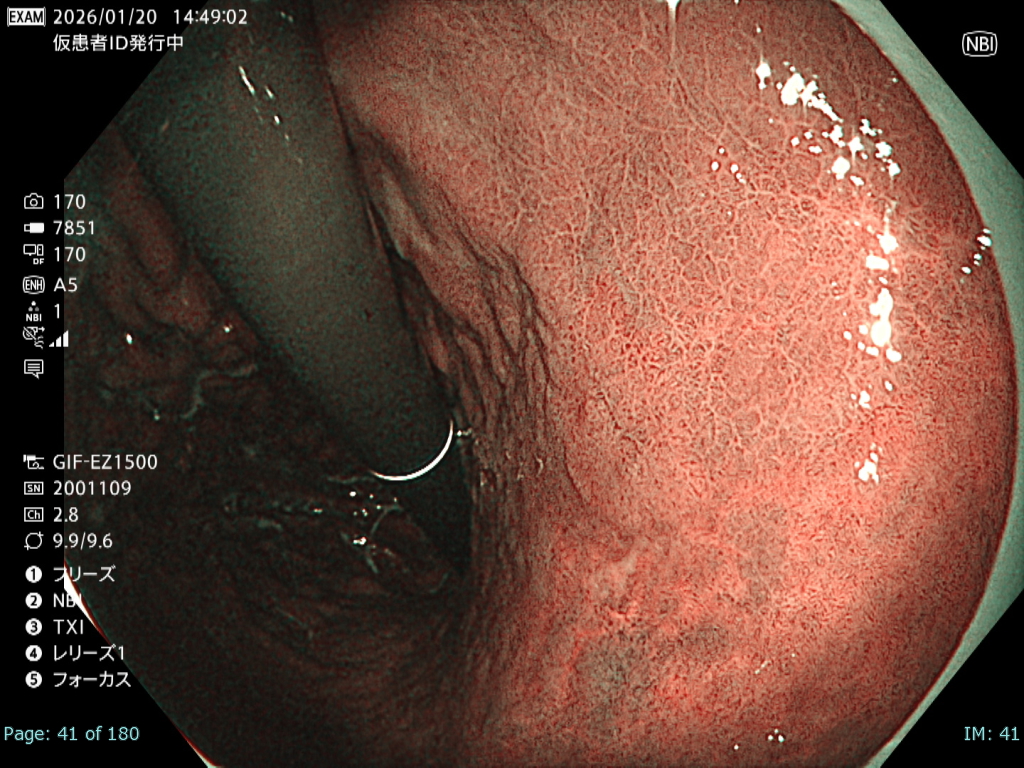

• NBI観察①(中遠景)

強調設定:B8

図3

観察中に出血が増加し、頻回の洗浄が必要となった。さらに胃管症例であったことから咳嗽が出現し、霧が生じるなど観察条件は不良であった。

• NBI+TXI観察① (中遠景)

切替前 NBI強調設定:B8

NBI+TXIレベル:中

図4

前述のとおり厳しい状況下でも、NBI+TXI観察モードは、NBI観察と比較して病変をよりシャープに描出出来ると感じた。